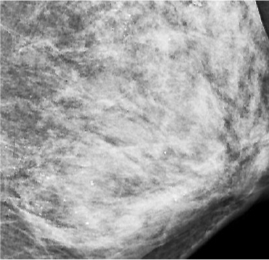

在X光片下,朱女士的乳腺里滿(mǎn)是星星點(diǎn)點(diǎn)的鈣化灶。在X光片下,朱女士的乳腺里滿(mǎn)是星星點(diǎn)點(diǎn)的鈣化灶。

武漢晚報(bào)訊(記者劉璇 通訊員譙玲玲 楊俠) 女子左側(cè)乳房里發(fā)現(xiàn)數(shù)不清的細(xì)沙樣鈣化灶,在X光片上看著好像“滿(mǎn)天星”。醫(yī)生推測(cè),極可能是她長(zhǎng)期在外按摩保養(yǎng)乳房時(shí)用力過(guò)猛損傷乳腺所致。

最讓醫(yī)生意外的是她的左側(cè)乳房。乳腺X線檢查時(shí),發(fā)現(xiàn)里面全部都是細(xì)小如沙子一樣的鈣化灶,布滿(mǎn)整個(gè)乳腺。讓管床醫(yī)生陶龍犯難的是,如此多的細(xì)小鈣化灶,無(wú)法判斷哪些是良性哪些是惡性。